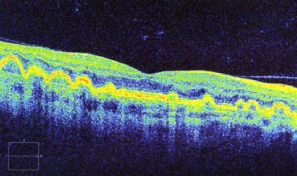

Optical Coherence Tomography uses low intensity infra-red light to give a 3D image of the back of the eye. It shows not only the surface but also the depth of the structures. It is similar to using ultrasound and creates an image not unlike an MRI or CT scan.

The instrument is incredibly good at measuring and monitoring Macular Degeneration. It can measure the thickness of the optic nerves which are affected by Glaucoma (and compare to an age, gender and ethnically matched normal).

In both circumstances it can mathematically show any changes from one visit to the next, working at a level way beyond the ability of even the most experienced observer with normal viewing methods.